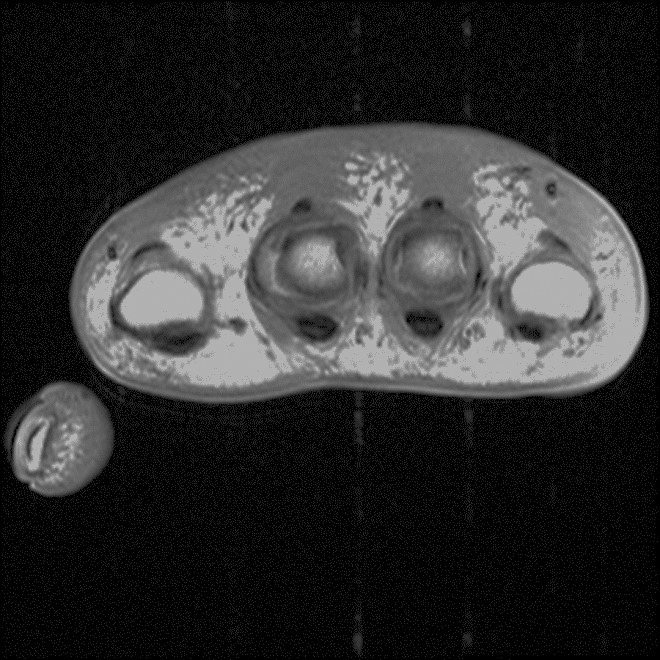

Radio-frequency Interference Artifact. Zipper-like linear bands of increased signal intensity are seen on axial T1-weighted MR image of the hand.